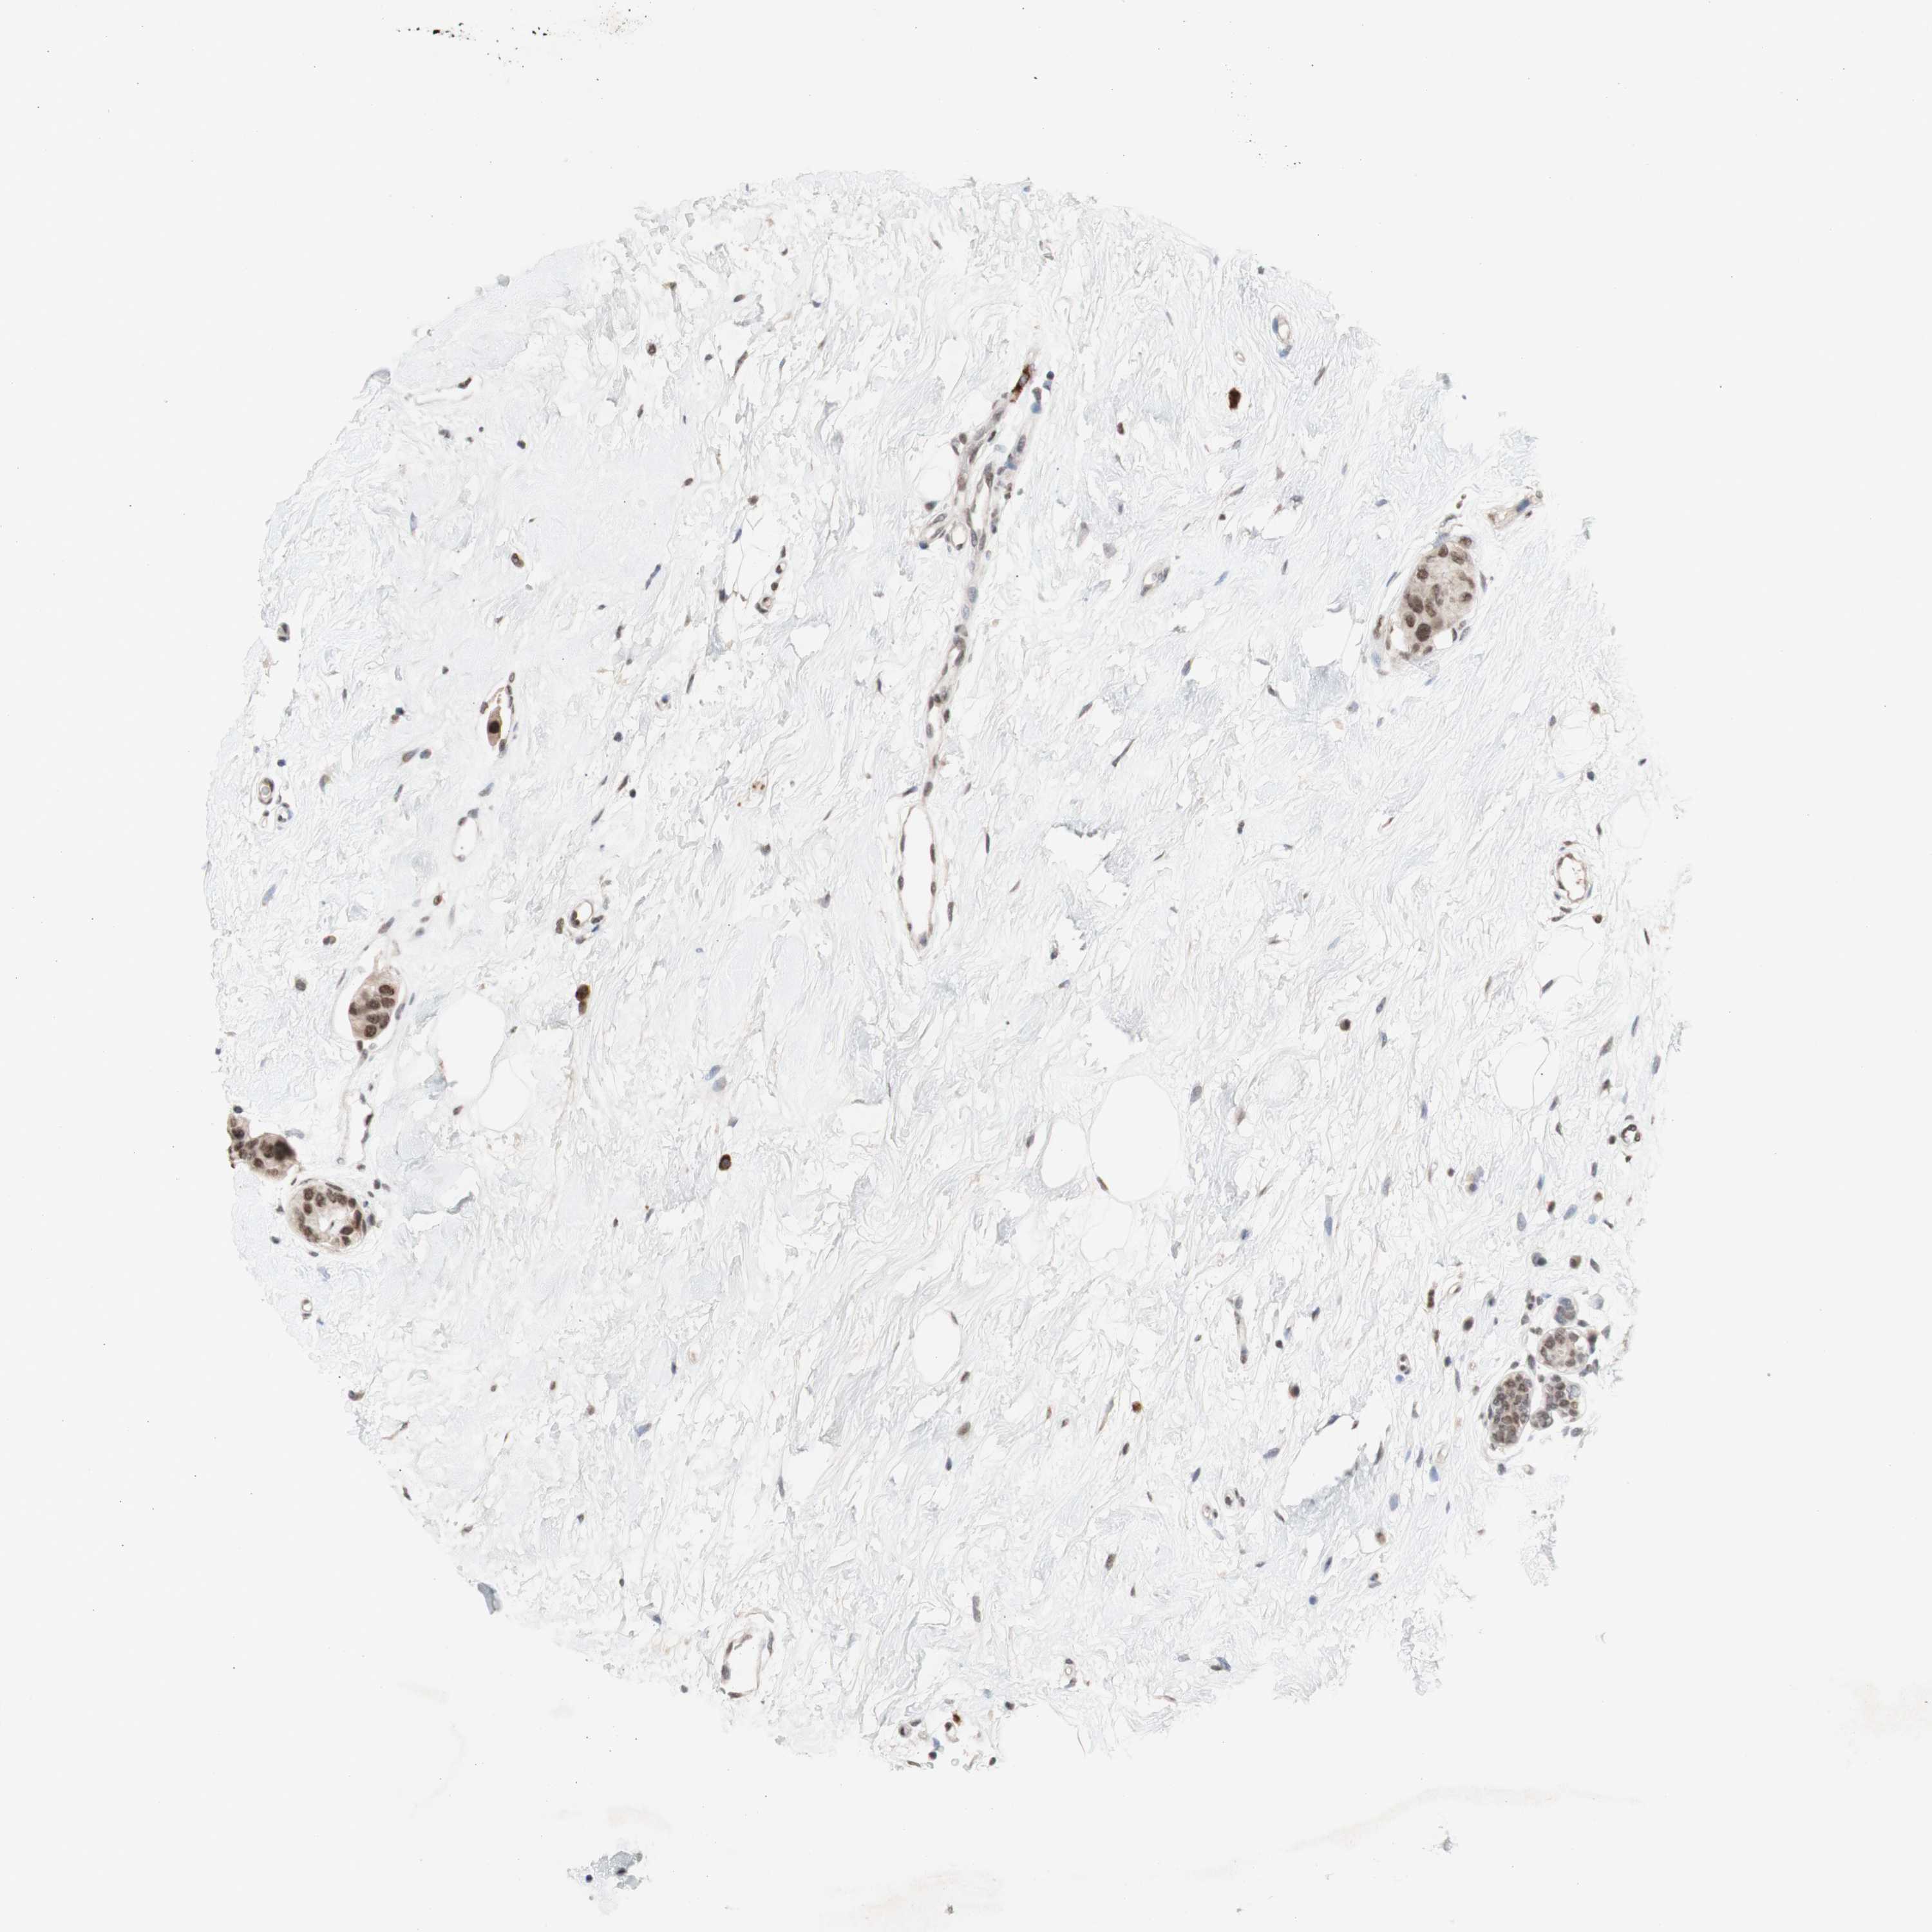

CANCER BREAST CANCER Show tissue menu

BRCA TCGA BRCA VALIDATION PROTEIN EXPRESSION

ANTIBODIES

AND

VALIDATION